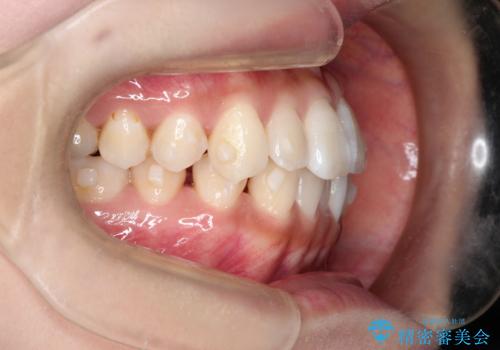

前歯のがたつきと反対咬合 インビザラインによる矯正治療

- 前歯のがたつきと反対咬合を主訴に来院されました。

下の前歯のがたつきを改善するために、右下の奥歯を後方に移動させるのと、歯と歯の間をわずかに削り、歯を並べる計画としました。

前歯の正中のずれを修正するのに少し時間がかかりましたが、整った歯並びにすることができました。